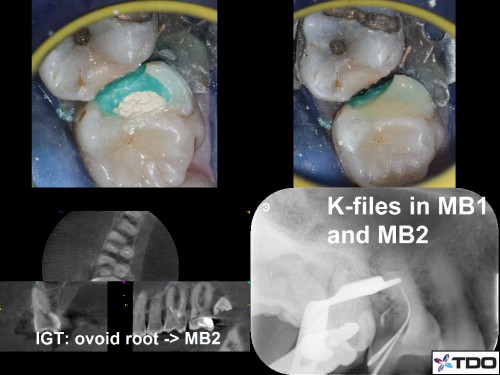

Restoring with Amalgam. 72yom. The patient had avoided the dentist due to dental anxiety. Tooth #3(16) SIP and #2(17) responded normally to all clinical tests. I recommended attempting to save both molars but he hesitantly agreed to start with tooth #3. Image Guided Treatment using CBCT aided in confirming the presence and location of MB2. The Opaldam matrix, first described by Dr. Michael Trudeau, is useful when using amalgam to restore teeth with deep interproximal caries especially when one or more corners are lost. In the end, the patient elected to extract the second and third molars and the amalgam restoration was incorporated into a Deep Margin Elevation for crown placement.